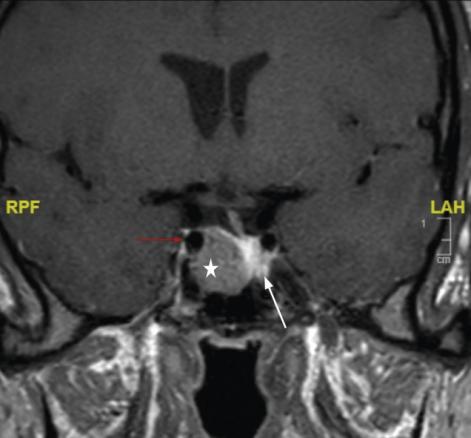

La réalisation d’une IRM hypophysaire permet de visualiser la tumeur (fig. 3, 4 et 5), d’évaluer sa taille et son éventuelle extension aux structures adjacentes.